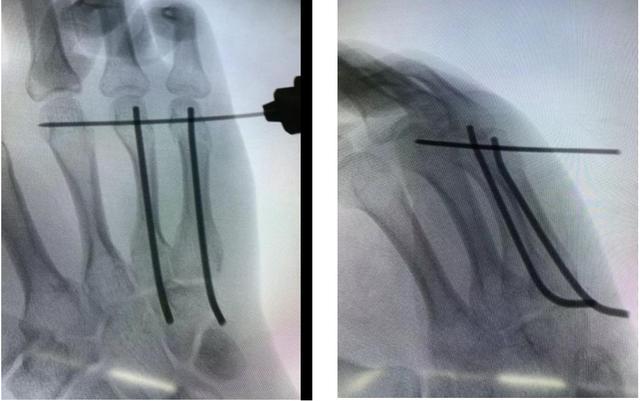

术中,谢毅凌副主任医师通过准确掌骨基底部开口,避开伸肌腱,置入2根预弯髓内针复位骨折,横向钢针利用自体掌骨作为支架,控制旋转,只需3个小针孔,30分钟即完成了手术治疗。

在微创下行右第4.5掌骨颈骨折闭合复位克氏针固定手术。

术中透视畸形纠正。